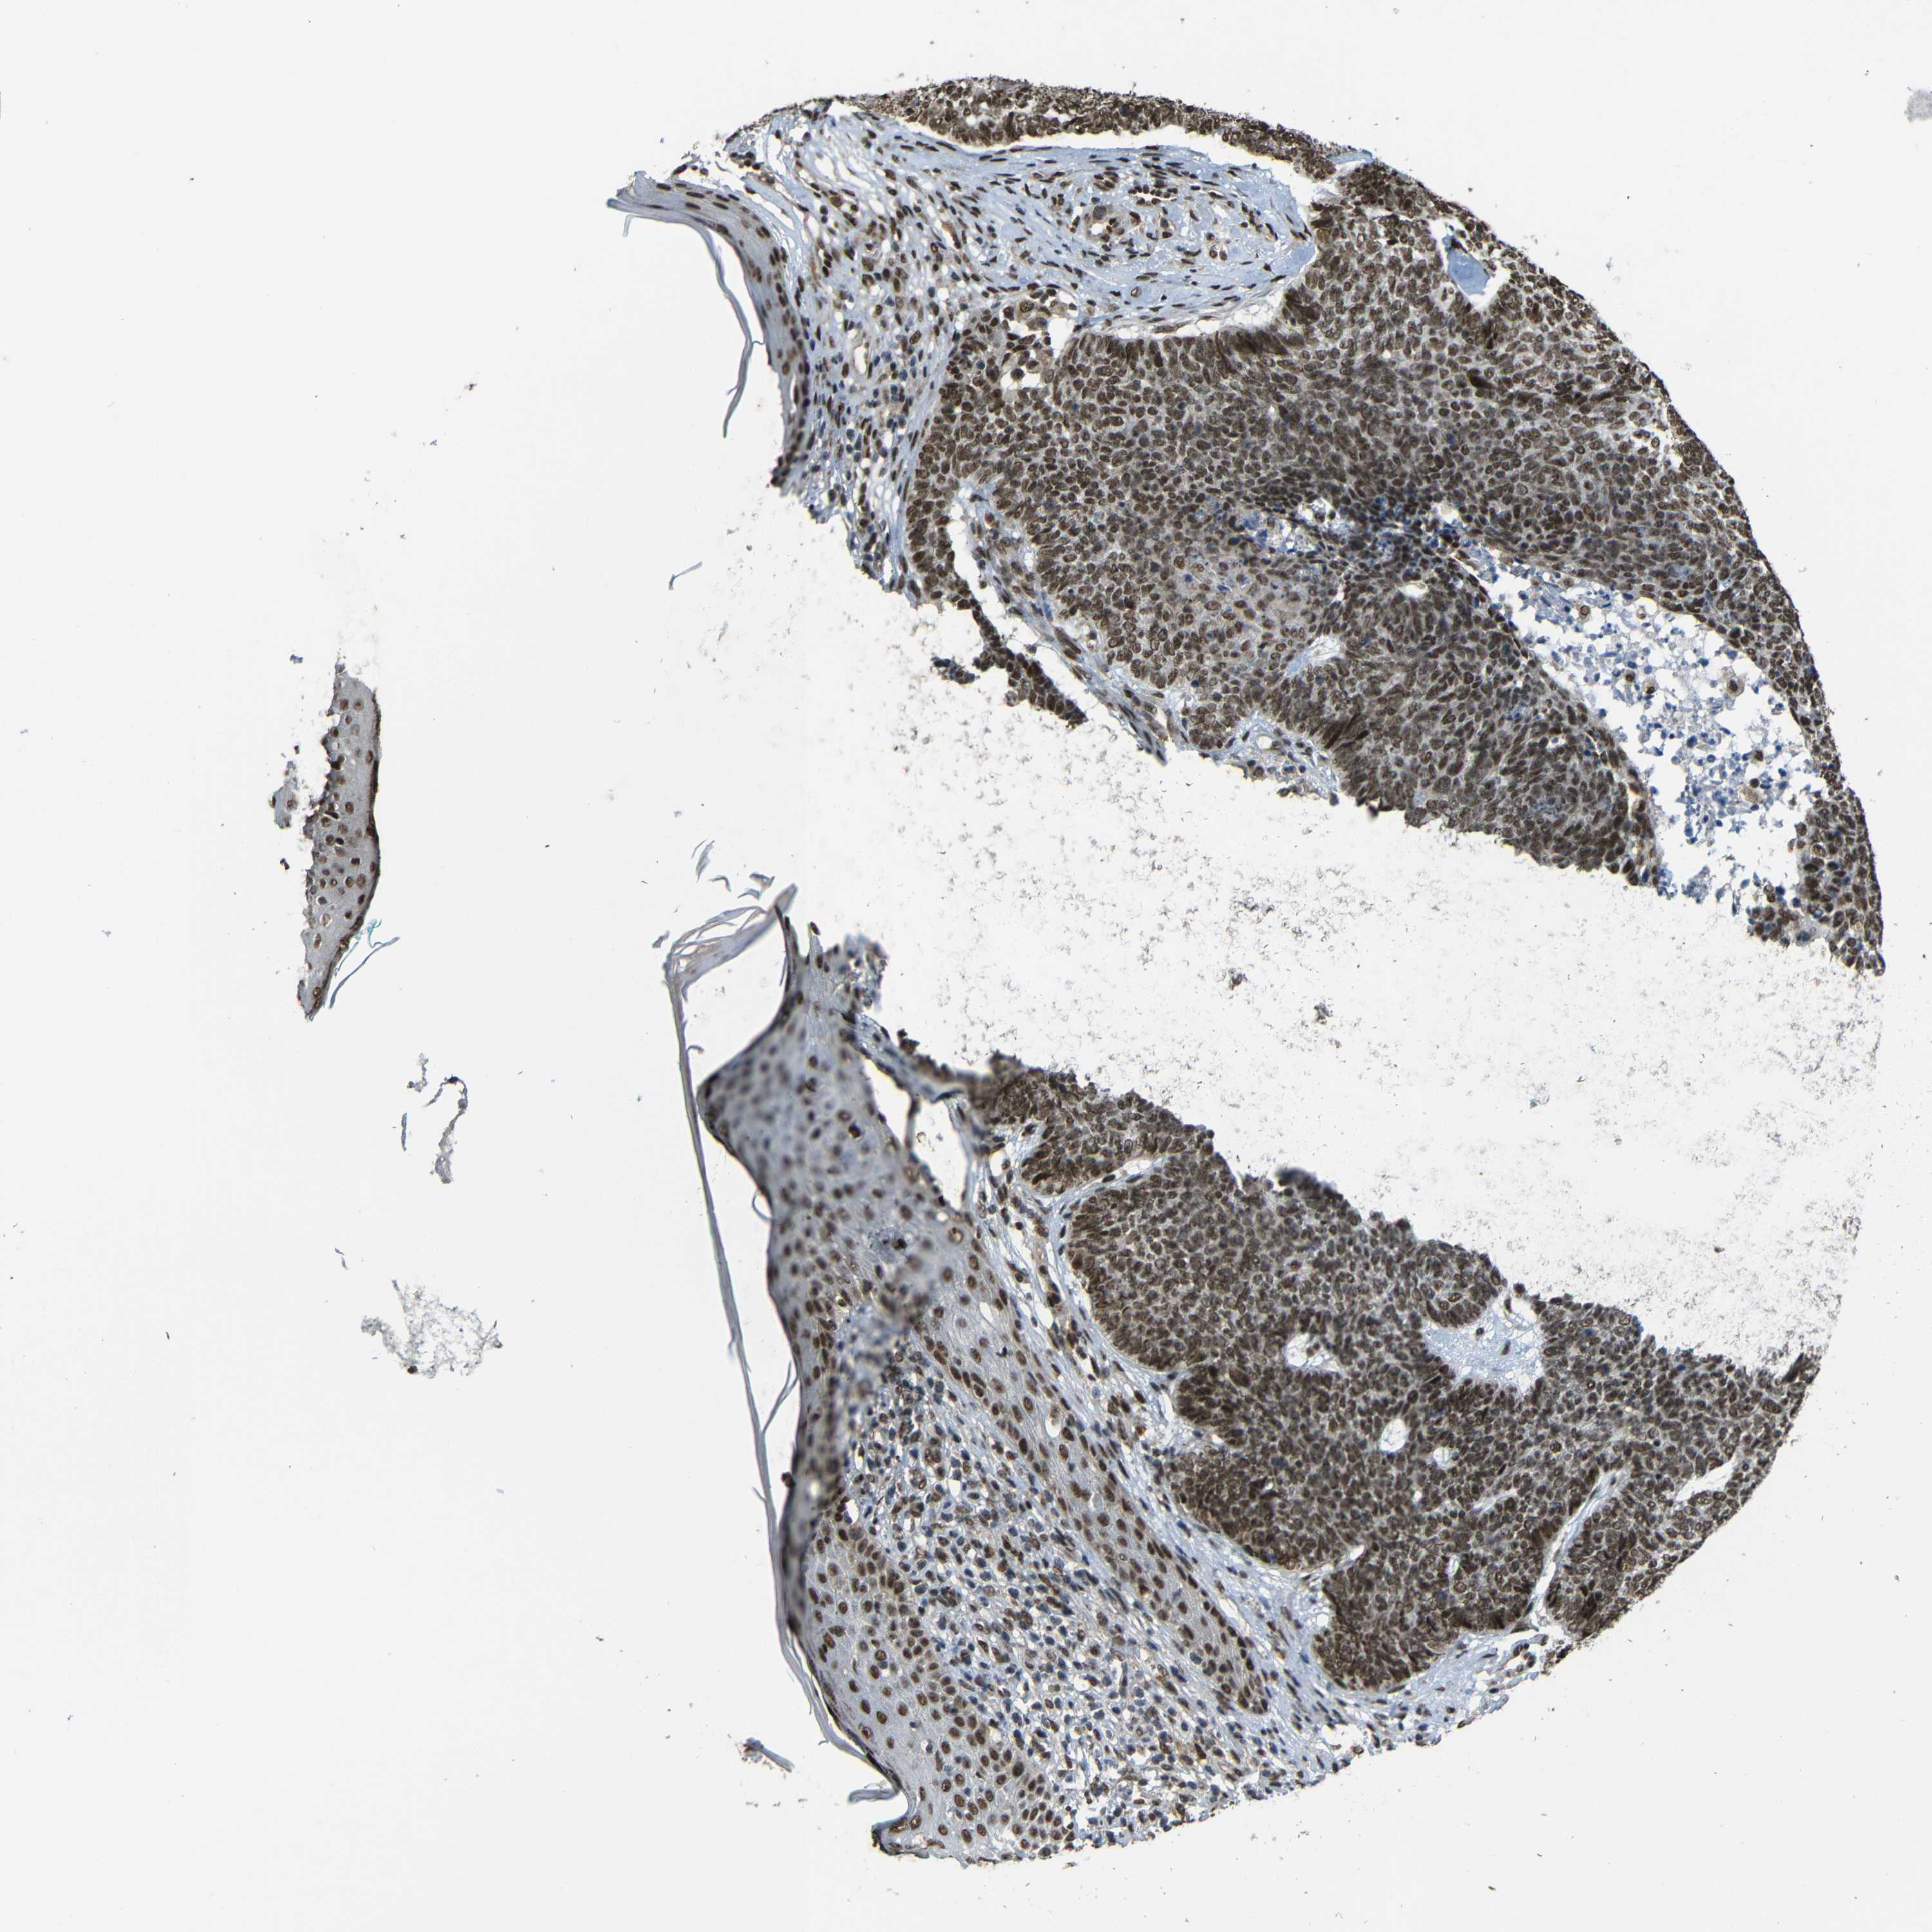

Basal cell and squamous cell cancer

SKIN CANCER - Protein expressioni

A mouse-over function shows sample information and annotation data. Click on an image to view it in a full screen mode. Samples can be filtered based on level of antibody staining by selecting one or several of the following categories: high, medium, low and not detected. The assay and annotation is described here.

Antibody stainingi

Antibody staining in the annotated cell types in the current human tissue is reported as not detected, low, medium, or high, based on conventional immunohistochemistry profiling in selected tissues. This score is based on the combination of the staining intensity and fraction of stained cells.

Each image is clickable and will lead to virtual microscopy that enables deeper exploration of all samples and also displays staining intensity scores, fraction scores and subcellular localization as well as patient and tissue information for each sample.

Antibody CAB013535

Staining

High

Intensity

Strong

Quantity

>75%

Location

Nuclear

Squamous cell carcinoma, NOS

Basal cell carcinoma